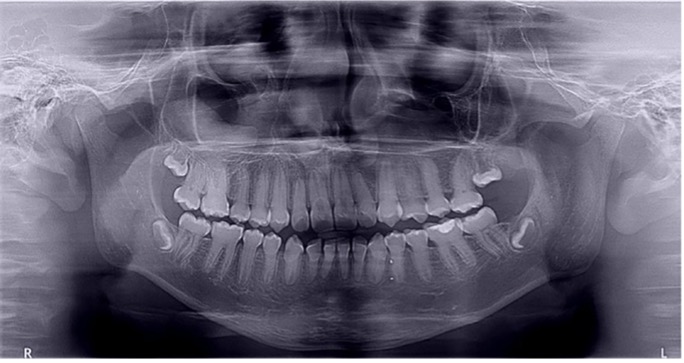

El examen clínico intraoral reveló alteración de la estructura y color de las piezas primarias, atrición y pérdida de la dimensión vertical (Figura 2). Radiográficamente se observó la presencia de coronas con marcada constricción cervical y raíces cortas (Figura 3). Presentaba alto riesgo cariogénico, por la presencia de lesiones de caries activas y dos restos radiculares, sumado a la anomalía estructural de la dentina (riesgo biológico específico) y bajo riesgo gingivoperiodontal. El riesgo socio-económico era alto por provenir de una familia con marcadas limitaciones económicas. Luego de la anamnesis, examen clínico y radiográfico, e interconsulta con el médico de cabecera se estableció el diagnóstico de DI Tipo I asociado a OI tipo I. Se planificó un tratamiento integral y preventivo con los objetivos de devolver forma y función, y proteger y evitar el desgaste de los tejidos conductas que pudieran interferir con el tratamiento.

Figura 3: Radiografía panorámica año 2007